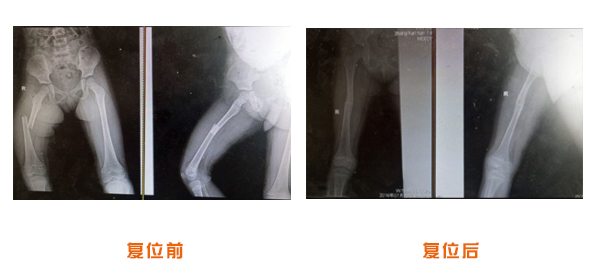

復位前后對比

肘關節脫位骨折治療前后對比